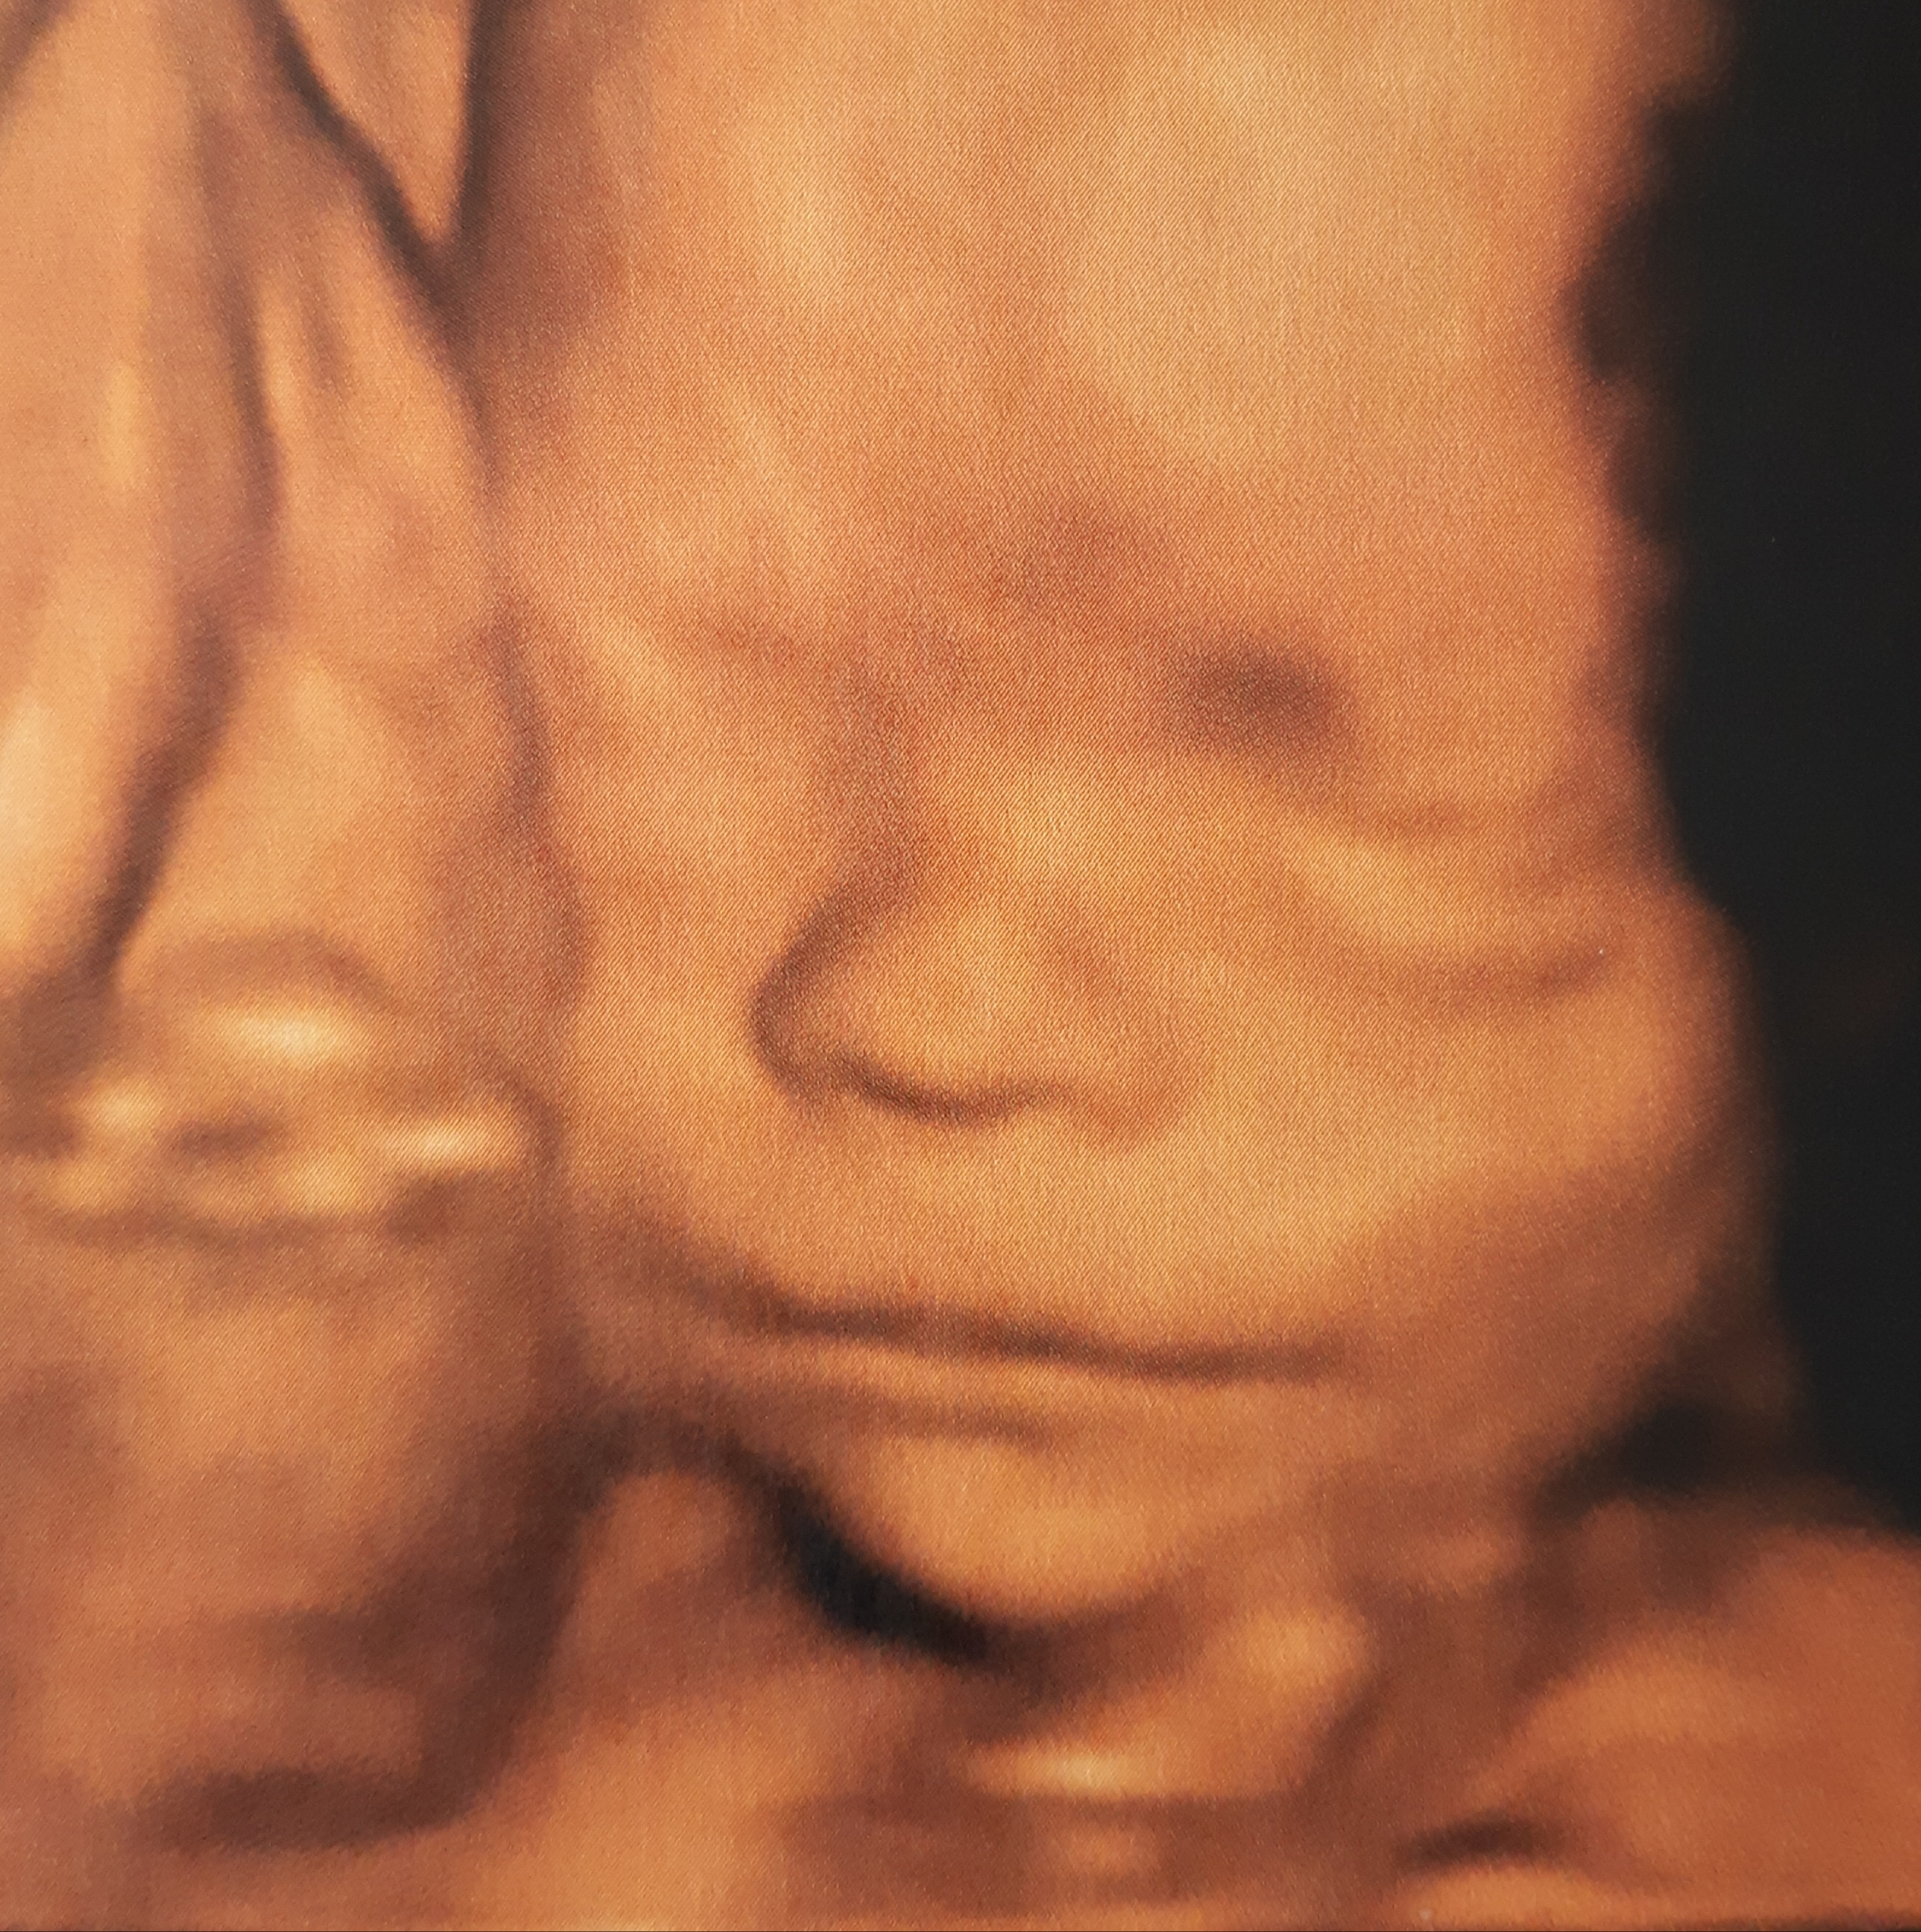

Quant à l’échographie en 3D, elle vous sera proposée bien sûr, mais dans la mesure du possible, car l’échographiste dépend toujours du bon vouloir du bébé et des conditions d’examen !